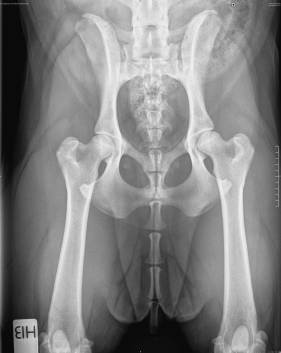

HD A/B

HD : B (A/B)

AD: 0/0